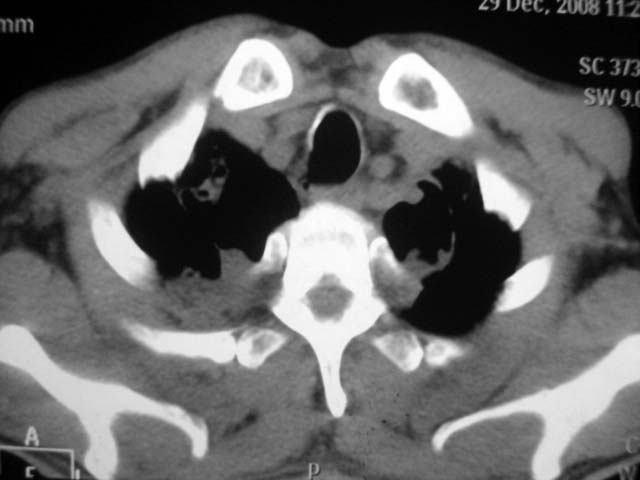

男,52岁,发热2月,糖尿病史。

抗结核治疗irpz方案,血糖未治疗,空腹15.9左右。症状无好转,左胸痛。

3、纵隔内淋巴结肿大。

结果:两肺继发性肺结核并曲霉菌感染。